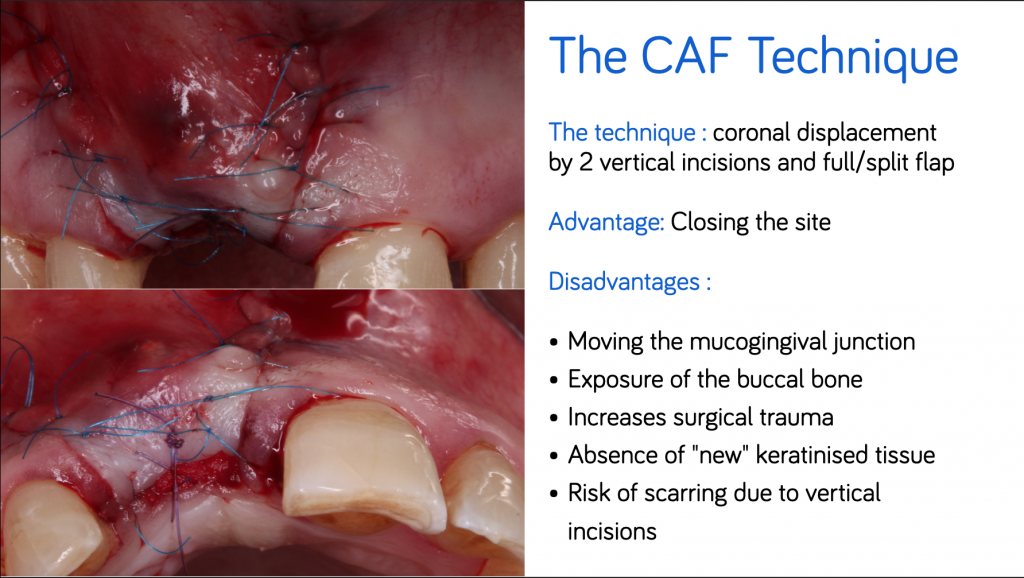

#1. The CAF

The CAF provides healing by first intention. It involves the realization of two incisions of vertical discharges and an incision in a partial thickness of the buccal flap, which strongly reduces the vascular supply.

From an esthetic point of view, incisions of discharges can cause visible scars in a patient with a line of the high smile as well as a displacement of the mucogingival line.